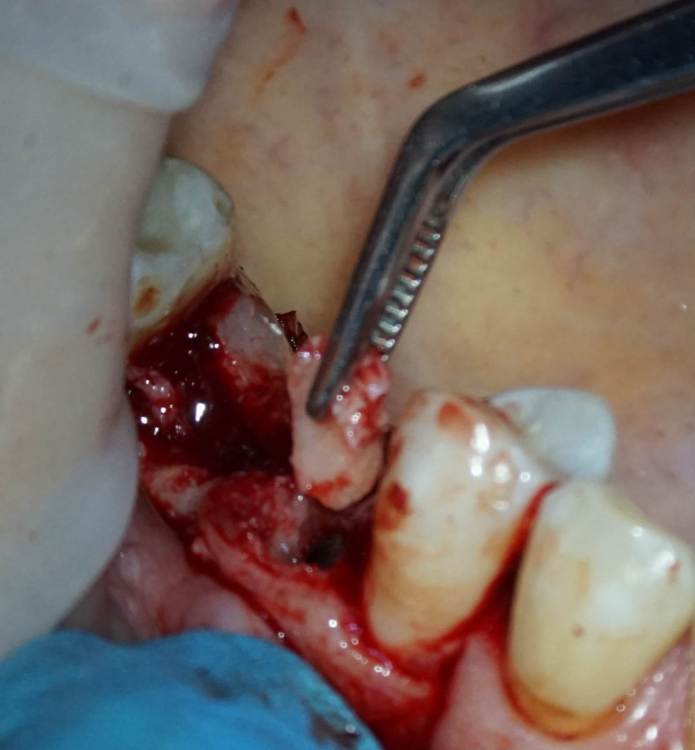

TIGER Опубликовано 8 мая, 2023 Автор Поделиться Опубликовано 8 мая, 2023 Всем привет!планировал удаление,но во время синуса решил использовать фрагмент как клин для стабилизации болта,в итоге совершил ошибку с более медиальной позицией 26,ибо шаблон не изготовил....через 5 мес одел времяхи,т.к будет тотал Ссылка на комментарий